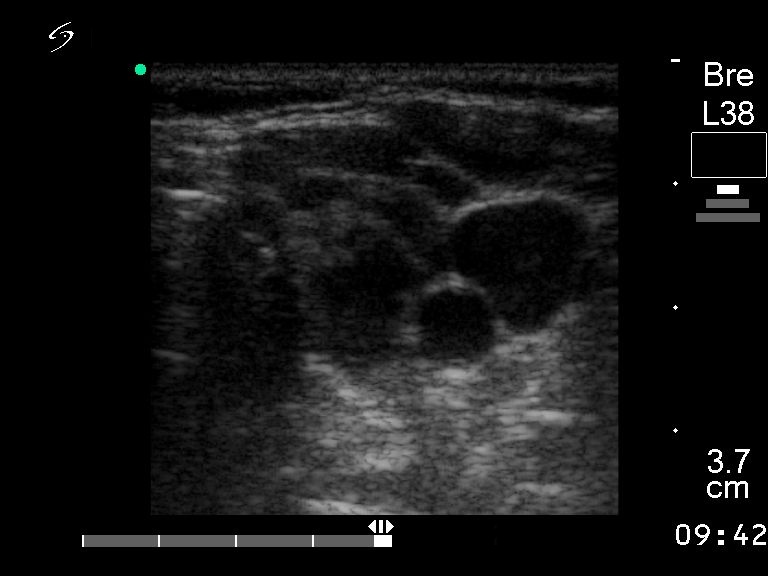

First examination (first and second rows of images):

Clinical presentation: a 55-year-old woman with hypothyroidism replaced with 50 ug levo-tiroxin.

Functional state: euthyroidism.

Ultrasonography: the echogenicity index is around 50% in both lobes. The circumscribed lesions are not nodules. Previous US diagnosis was multinodular goiter.

Combined ultrasound-cytological report : benign Hashimoto's thyroiditis.